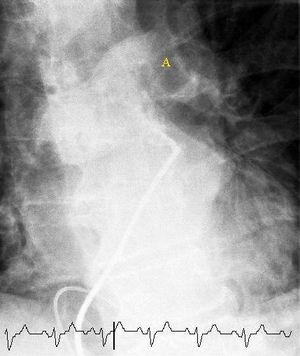

(A) After inhalation of 20 mCi of Xenon-133 gas, scintigraphic images were obtained in the posterior projection, showing uniform ventilation to lungs.

(B) After intravenous injection of 4 mCi of Technetium-99m-labeled albumin, scintigraphic images shown here in the posterior projection. This and other views showed decreased activity in multiple regions.

مسح التهوية/التروية الرئوي

مسح التهوية والتروية الرئوي هو شكل من التصوير الشعاعي التشخيصي هدفه تقييم التروية والتهوية في الرئتين ويستخدم في تشخيص الانصمام الرئوي، مبدأ عمله هو كالتالي:

- الجزء المتعلق بالتهوية يتم من خلال جعل المريض يستنشق هواء يحتوي على غاز الزينون أو التكنيشيوم.

- الجزء المتعلق بالتروية يتم فحصه من خلال حقن المريض بالتكنيشيوم أو أي صبغة مشعة.

- يتم تصوير الصدر بكاميرا غاما عقب ذلك.

استخدام هذه التقنية أقل شيوعاً من الالتصوير الطبقي المحوسب للرئة وذلك لعدم توفر هذه التقنية في كل المستشفيات كما أن دقة الالتصوير الطبقي المحوسب للرئة أصبحت أعلى، تستخدم هذه التقنية حالياً في حالات الحمل والحساسية للصبغات المشعة أو اليود المشع.[21]